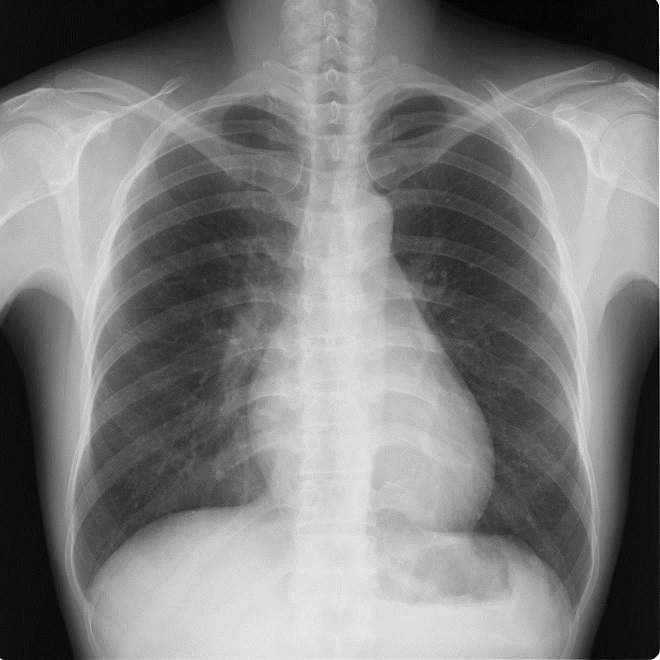

何処に異常陰影があるでしょうか?

肩甲骨に重なって見逃しやすいが、仮骨形成が始まった右第7肋骨骨折を診断できる。

右第4肋骨と胸椎の肋骨頭関節に関節面に一致して陰影をみとめる。

左鎖骨、胸鎖関節に近接した約1.5cmの円形陰影があり、辺縁は不規則(毛羽立ってみえる)になっている。陰影は大動脈・縦隔とのシルエットサインはみられず左肺S1+2に存在すると考えられ、肺門部のリンパ節腫脹はみられない。

縦隔陰影の拡大、大動脈の拡張をみとめる。右肺門肺動脈に重なって半球様の陰影(径2.7cm)が確認できる。肺門のリンパ節腫大等はない。

[評価]S6の炎症性偽腫瘍、結核、肺がん等の可能性がありCT等の検索・喀痰細胞診・生検が必要になる。